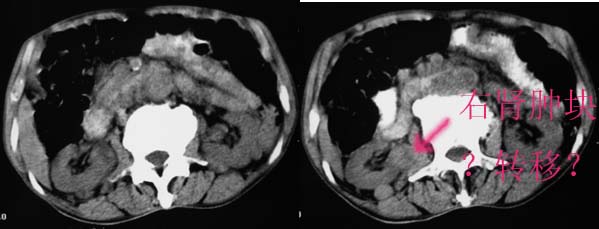

右侧肾上腺区可见软组织密度肿块,密度欠均匀,未见钙化;右肾下极内侧可见实质局限性增厚并呈肿块样突出肾轮廓.

右肾肿块为原发灶??还是转移??

右侧肾上腺区软组织肿块影,密度不均,其周围及腹主动脉周围,心包周围均见多个淋巴结肿大.结合临床首先考虑:右肾上腺恶性肿瘤伴腹腔内及心包淋巴结转移.

综合上述表现及临床,首先考虑右侧肾上腺及腹腔,腹膜后淋巴结转移.其次考虑淋巴瘤.

右肾肿块为原发灶??还是转移??建议活检(既然大腿及腋下有结节,很方便吗)。